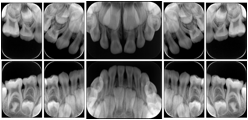

Intra-oral radiography typically involves acquisition of multiple images of various parts of the dentition. Many digital radiographic systems offer customized templates that are used for displaying the images in a study on the screen. These templates may also be referred to as mounts or view sets. The Structured Display Object represents a standard method of encoding and exchanging the layout and intended display of Structured Displays. A structured display object created in this manner could be stored with a study and exchanged with images to allow for complete reproduction of the original exam.

1. A patient visits a General Dentist where a Full Mouth Series Exam with 18 images is acquired. The dentist observes severe bone loss and refers the patient to a Periodontist. The 18 images from the Full Mouth Series along with a Structured Display are copied to a DICOM Interchange CD and sent with the patient to see the specialist. The Periodontist uses the CD to open the exam in his Dental Radiographic Software and consults via phone with the General Dentist. Both are able to observe the same exam showing the images on each user's display using the exact same layout.

Intra-oral Full Mouth Series Structured Display

Figure OO-1. Intra-oral Full Mouth Series Structured Display

In most standard cases, images are oriented in structured layouts. These structured displays are useful to be shared between providers for reference purposes.